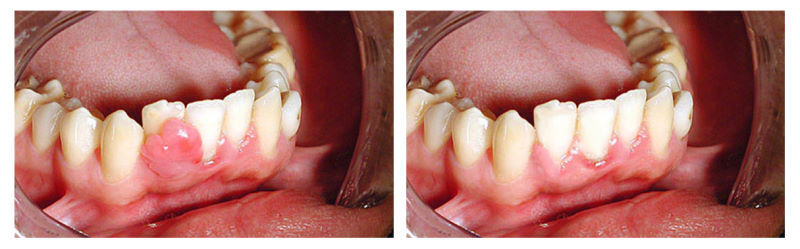

• Цистотомия. Врач формирует в десне отверстие и вскрывает кистозную капсулу. Далее проводится ревизия тканей и удаление некротизированных участков. Затем полость промывается и заполняется тампоном с лекарством. Раз в несколько дней тампон меняется. Лечение продолжается до полного выздоровления.

• Цистэктомия. Радикулярная киста зуба удаляется путем отделения ее оболочки от прилегающих костных тканей либо вместе с частью пораженного корня. В образовавшееся пространство вводится специальный костеобразующий препарат.